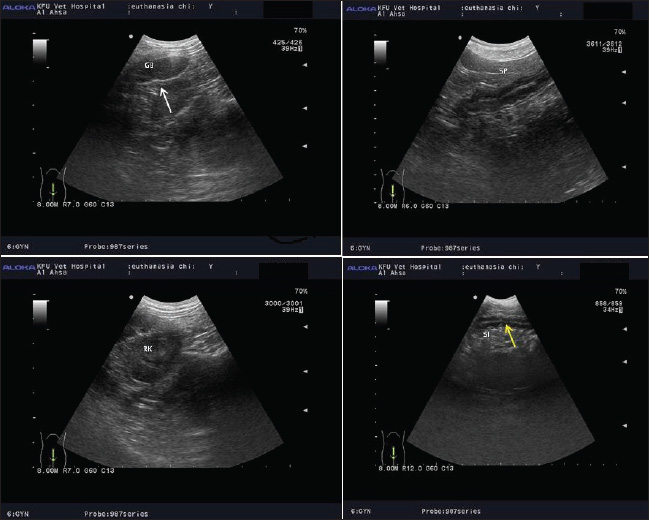

Fig. 3. The internal organs show reduction in echogenicity with unclear organ architecture at 2 and 4 hours after induction of euthanization at different times. Notably, the irregularity in the mucosa of gall bladder (whit arrow), irregularity of mucosa of small and large intestine (yellow arrow), changes in liver echogenicity, and unclear of vascularity in splenic paryenchyma were noticed at 2 and 4 hours after induction of death.

Notably, the irregularity in the mucosa of the gallbladder is a hallmark of early autolytic changes. The gallbladder is particularly prone to postmortem alterations due to its high content of digestive enzymes and bile, which can lead to enzymatic digestion of the mucosal lining. Histological studies have shown that mucosal desquamation and epithelial breakdown can occur within 1–4 hours after death, particularly in warm environments (Klimkowski et al., 2022).

Similarly, the irregularity of the mucosa in the small and large intestines (yellow arrow) reflects the early stages of autolysis. The gastrointestinal tract is one of the first organ systems to undergo decomposition because of its high bacterial load. The intestinal mucosa is rapidly disrupted as bacteria proliferate and tissue hypoxia progresses. Mucosal sloughing and submucosal edema can be observed as early as 2–4 hours postmortem (Pérez et al., 2020).

In addition, changes in liver echogenicity observed via ultrasonography indicate progressive hepatic cell lysis and the accumulation of intrahepatic gas or fluid due to autolysis and early putrefaction. Due to its large volume and rich blood supply, the liver undergoes predictable postmortem changes that can be detected within hours after death. The echogenicity may initially decrease due to fluid infiltration and increased cellular breakdown, but it later becomes heterogeneous due to gas formation (Wu et al., 2021).

Moreover, unclear vascularity in the splenic parenchyma may reflect early autolytic disruption of the splenic tissue architecture. The spleen typically softens and loses its definition as proteolytic enzymes break down cellular and connective tissues. Moreover, loss of vascular clarity can be associated with hemolysis and blood settling (livor mortis), which distorts normal imaging features (Roccarina et al., 2024).